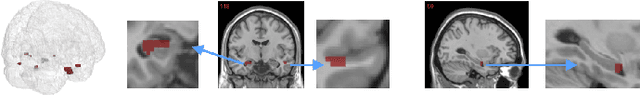

The prediction and selection of lesion features are two important tasks in voxel-based neuroimage analysis. Existing multivariate learning models take two tasks equivalently and optimize simultaneously. However, in addition to lesion features, we observe that there is another type of feature, which is commonly introduced during the procedure of preprocessing steps, which can improve the prediction result. We call such a type of feature as procedural bias. Therefore, in this paper, we propose that the features/voxels in neuroimage data are consist of three orthogonal parts: lesion features, procedural bias, and null features. To stably select lesion features and leverage procedural bias into prediction, we propose an iterative algorithm (termed GSplit LBI) as a discretization of differential inclusion of inverse scale space, which is the combination of Variable Splitting scheme and Linearized Bregman Iteration (LBI). Specifically, with a variable the splitting term, two estimators are introduced and split apart, i.e. one is for feature selection (the sparse estimator) and the other is for prediction (the dense estimator). Implemented with Linearized Bregman Iteration (LBI), the solution path of both estimators can be returned with different sparsity levels on the sparse estimator for the selection of lesion features. Besides, the dense the estimator can additionally leverage procedural bias to further improve prediction results. To test the efficacy of our method, we conduct experiments on the simulated study and Alzheimer's Disease Neuroimaging Initiative (ADNI) database. The validity and the benefit of our model can be shown by the improvement of prediction results and the interpretability of visualized procedural bias and lesion features.